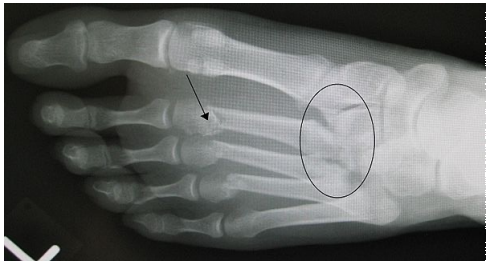

what xray sign can we see in lisfranc injuries

gap between base of 1st and 2nd proximal metatarsals

Pt presents with pain and swelling over midfoot and bruising on sole of foot following a fall from height, what is your primary hypothesis for diagnosis without imaging

Lisfranc injury

Pt presents with pain over midfoot after dropping a couch on foot whilst moving house, upon xray inspection you find a gap between base of 1st and 2nd proximal metatarsals, what is your primary hypothesis for diagnosis

What specific xray view is most specific for detecting lisfranc injuries

weight bearing AP view